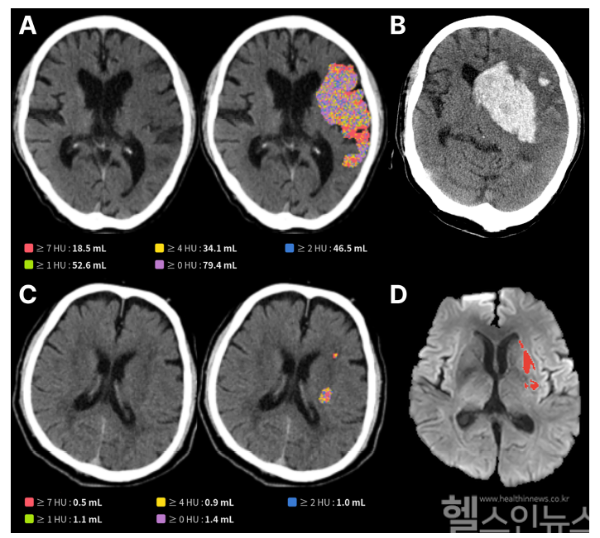

제이엘케이의 AI는 NCCT와 DWI 데이터를 학습한 딥러닝 기반 모델로, 육안으로 식별하기 어려운 병변도 감지하고 부피까지 정량화한다. 연구는 국내 6개 뇌졸중 센터에서 재개통술 환자 603명을 대상으로 진행됐다.

결과에 따르면, CT 영상상 손상 부피가 50mL를 초과할 경우, 환자의 3개월 후 기능 회복률은 17.3%에 불과했으며, 심각한 합병증 발생률은 66%에 달했다. 반면 손상 부피가 작을 경우 회복률은 54.2%로, AI 분석 결과가 환자 예후와 밀접한 관련이 있음을 입증했다.